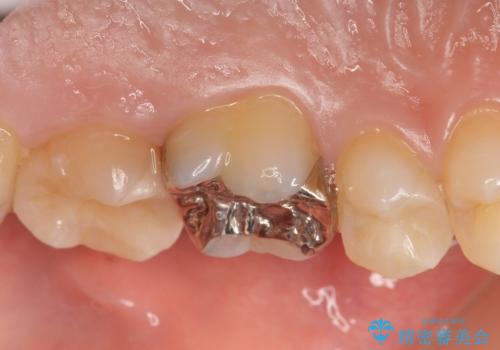

- 健診で虫歯があると言われたので診て欲しいといらっしゃった方の症例です。

左上5、6、7番目の歯に虫歯を認めたため、左上5、7はセラミックインレーによる修復を行いました。

左上6に関しては患者様の希望でパラジウムインレーによる修復を行いました。